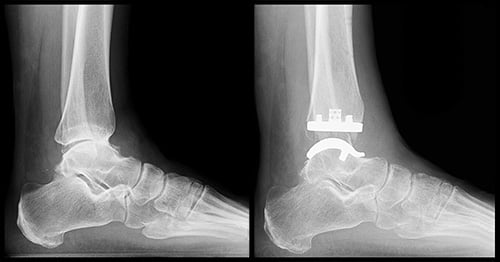

Lateral (side view) and anteroposterior (front view) X-rays showing end-stage arthritis with bone-on-bone contact in the ankle joint.

What is replaced in an ankle replacement?

The surface of the tibia and talus that make up the ankle joint is removed. In their place, metal pieces are inserted into the bone. Then, a plastic insert it attached to the metal piece on the tibia. In a replacement, the metal piece on the talus will rub against the plastic piece attached the tibial implant. This takes away the pain for the ankle arthritis and preserves the motion in the joint.

Lateral (side view) and anteroposterior (front view) X-rays showing the implants of a total ankle replacement.